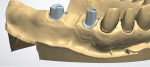

Upper provisional restorations were fabricated from the diagnostic wax-up using a PVS matrix, with the posteriors retained on temporary abutments.9 The posterior crowns would be fabricated from layered zirconia for strength and opacity to block out the underlying metal abutments. The anterior crowns would be lithium disilicate due to the enhanced esthetic quality of that material. The visual length of the maxillary implant teeth was determined in the laboratory first (Figure 6 through Figure 10), with the clinical gingival management done at the seat appointment. Slight occlusal adjustment was needed on the mandibular arch to create bilateral equal posterior contact in occlusion. The patient returned the following day for impressions of the provisional restorations and photographs, and to obtain centric occlusion records. The record was taken by creating a small direct composite deprogrammer on the palatal surface of teeth Nos. 8 and 9, opening the bite 0.5 mm.10 The maxillary posterior provisional restorations were removed, tall healing caps were placed in the implants, and a bite registration was taken. Healing caps were removed and sent with the case to the laboratory for mounting.

From the diagnostic mounting, a blueprint of the final restorations was generated to guide the patient's treatment decisions and create matrices for the provisional restorations. In the dental laboratory, a soft-tissue model was poured to replicate the patient's clinical situation. Before designing the custom milled abutments, and with the diagnostic cast as a reference, the dental technician was able to alter the soft-tissue coronal to the implant fixture (Figure 6 through Figure 8). Preparing the tissue prior to 3D scanning for the abutment design made it possible to control the emergence and create more visible tooth structure (Figure 9 and Figure 10), harmonizing with the gingival position of the anterior teeth and addressing the patient's concern with the visible length of the restorations.11